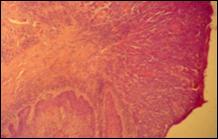

Histologic, se observa epiderm atrofic cu pierderea arhitectonicii normale, omogenizarea colagenului in treimea superioara a dermului, combinate cu zone de infiltrat limfocitar si histiocitar.

Leziunile seamana cu cele de lichen scleroatrofic descoperite in alte zone ale corpului.

Aspectul anatomo-patologic

Leziuni:

hipercheratoza

atrofie epiteliala

fibroza eozinofila > 4 mm

vacuolizarea celulelor membranei bazale

infiltrat inflamator difuz si focal subepitelial.

Figura 3. Aspect anatomopatologic